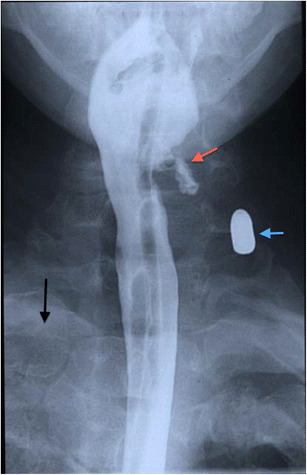

Contrast swallow assessment of a patient who sustained multiple penetrating gunshot injuries, including to the neck. A bullet is demonstrated in the soft tissues of the left zone 2 of the neck (blue arrow). A nasogastric tube was passed during the emergency trauma assessment and can be seen in situ. Haematoma is demonstrated in the left pyriform fossa with mucosal disruption and contrast leakage into the parapharyngeal tissues (red arrow). Note the opacification of the upper zone of the right hemithorax consistent with haemothorax (black arrow)